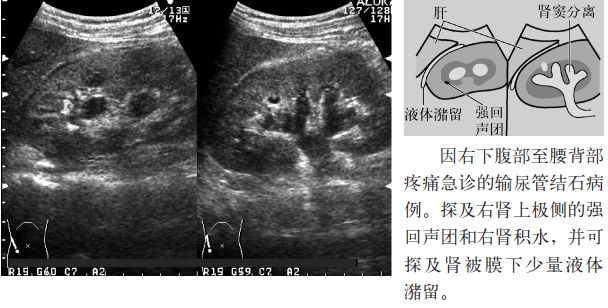

3.肾周围探及无回声区(肾盂尿自然外渗)。

图13 肾盂尿外渗

2.输尿管结石的间接征象是肾周围积液,是由于输尿管结石所致的肾盂内压力上升,尿液向肾盂外自然渗出所致,称为尿自然外渗。除输尿管结石外还可见于输尿管癌或输尿管转移癌、分娩及体外冲击波碎石术(extracorporeal shock wave lithotripsy,ESWL)后等。